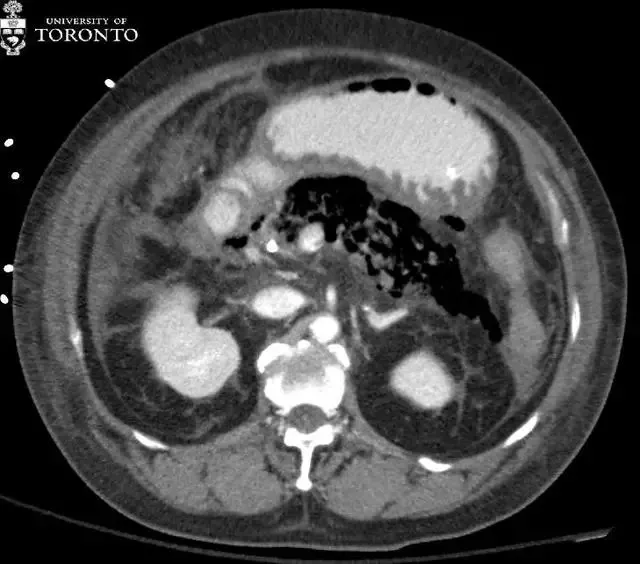

该患者被送入重症监护室 , 并给予高剂量抗生素静脉滴注 。 之后患者病情稳定 , 未进行手术治疗 。 两个星期后 , 患者白细胞计数升高 , 再次昏厥 。 入院当天的 CT 扫描显示广泛的胰腺坏死 。 胰腺组织几乎完全由气泡(红色箭头)所取代 。

诊断:患者被确诊为急性坏死性胰腺炎 , 且可能合并感染 。

为了评估胰腺炎的严重程度 , 通常应用多相流 CT (平扫 , 晚动脉期和静脉期) 。 急性胰腺炎的症状包括胰腺和胰周脂肪间隙的肿胀 。 其并发症包括静脉血栓形成 , 假性动脉瘤 , 腹膜后脓肿(可形成假性囊肿) , 胰腺坏死和感染 。

CT 是诊断胰腺坏死最好的方法 。 不增强的胰腺组织一般被认为是坏死 , 并且坏死的程度与疾病及预后的严重程度相关 。 胰腺坏死感染通常在症状发作后的前四个星期出现 。 约 40%到 70%的坏死性胰腺炎患者会发展为感染坏死 。 感染性胰腺坏死的患者通常病情较重且有中毒症状 , 预后较差 。

从历史经验上看 , 推荐早期积极进行手术清创 , 但延迟干预和导管引流已经表现出改善病情的效果 。 在 CT 上 , 出现气泡则提示感染 , 但仅有 15%的病例会出现 。 因此 , 对于感染坏死的诊断 , 临床和影像相结合是很有必要的 。